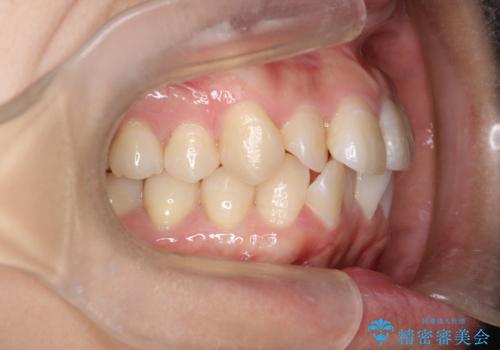

【インビザライン】前歯の凸凹をなおしたい

- 前歯の凸凹をなおしたいことを主訴にインビザラインにて矯正治療を行いました。

患者様にしっかりとインビザラインを使用して頂けたことで綺麗な仕上がりとなりました。